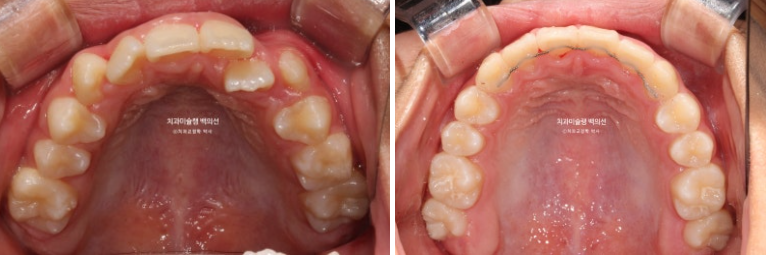

24년 1월 교정치료를 위해 온 만 10세 어린이 입니다.

3년 전에 소아치과에서 앞니 부분교정을 한 적이 있다고 합니다.

그래서 위 앞니에는 중절치 두 개를 잇는 철사유지장치가 붙어있었습니다.

중심선이 약 2mm 어긋나 있으며 위 앞니 치축은 한쪽으로 기울어져 있습니다.

앞니가 깊게 물리는 과개교합도 보입니다.

24.02

공간부족으로 인한 덧니가 심해 반대교합이 있습니다.

악궁확장을 통한 덧니배열을 목표로 인비절라인퍼스트 교정치료 권유드렸습니다.